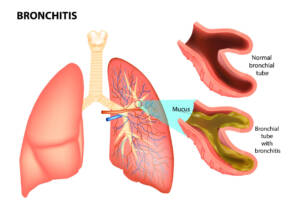

Nella Pneumologia: da utilizzare in caso di asma,

bronchiti,

BPCO e ipertensione polmonare.

- della patologia da discrasia ventilatoria polmonare